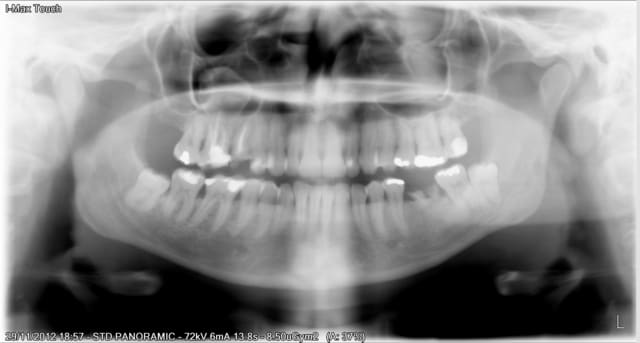

Paciente qui viens pour detartrage et enlever la racine d´en bas.

Petite surprise dans le sinus maxilaire droit. je pense qu´en relation avec la "belle" Endo de la 16.

J´ai envoye a l´O.R.L on est en attente du scanner.

J'avais pense au quiste muqueux neanmoins je trouve que sur ma pano c'est trop radiopaque, et il n'a pas la forme classique en dôme

La furcation de la dent 16, n,est pas top, je pense l'extraire, mais le sîte ne m'inspire pas pour poser un implant.

Patiente jeune 35 ans, aucun signe clinique. Elle me dit que l'endo doit avoir une dizaine d' années elle avait fait un bel abcess avec fistule.